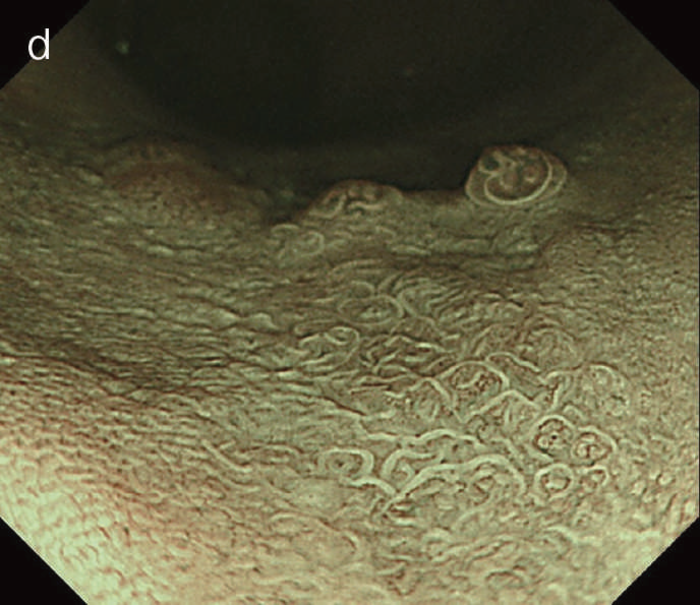

UCの活動期には,生検による病理診断において腫瘍性変化と炎症や再生異型との鑑別診断は困難であり,内視鏡診断においても炎症による修飾のため活動期に正確な内視鏡診断を行うことは困難である。UC診療における治療目標は内視鏡的寛解であるが,適切なサーベイランス内視鏡検査および発見病変への内視鏡診断のためにも炎症の寛解導入・維持を目指すべきである。UC関連大腸腫瘍の内視鏡診断は,その難易度が高く,複数の内視鏡modalityを用いて段階的に進めることが求められる。白色光,非拡大画像強調(NBIやBLI),拡大画像強調観察にて診断を進める。インジゴカルミンによる病変の性状を非拡大で病変範囲や凹凸を観察し,画像強調およびクリスタルバイオレット注)を用いた色素併用拡大観察で診断を絞り込む。 - 白色光および色素内視鏡検査による診断(形態的特徴)

図5 UC関連粘膜下層浸潤癌の内視鏡所見

- 白色光像:直腸(直腸S状部)の発赤調変化。背景粘膜は寛解期にあった。

- 色素内視鏡像:病変辺縁が明瞭となるが,病変肛門側で不明瞭であった。

- NBI拡大像:口径不同,不均一な微小血管と不整な表面構造所見を認めた。

- pit pattern像:小型の類円形,管状pitを認めた。